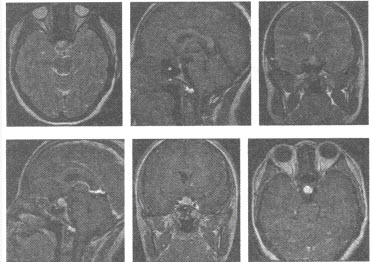

患者,男性,62岁,左上肢肌力下降1周,颅脑MRI平扫和增强扫描图像如下,应首先考虑为()

A:脑转移瘤

B:脑脓肿

C:脑胶质瘤

D:脑膜瘤

E:脑内血肿吸收期